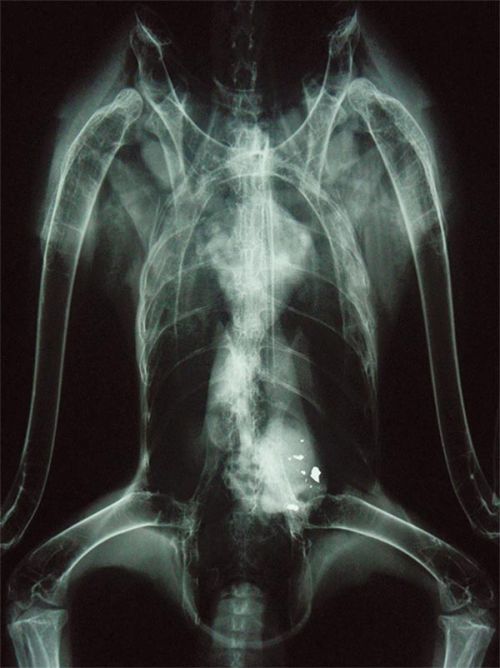

An X-ray shows lead ammunition in the gizzards of a bald eagle. Image courtesy of Avian Haven.